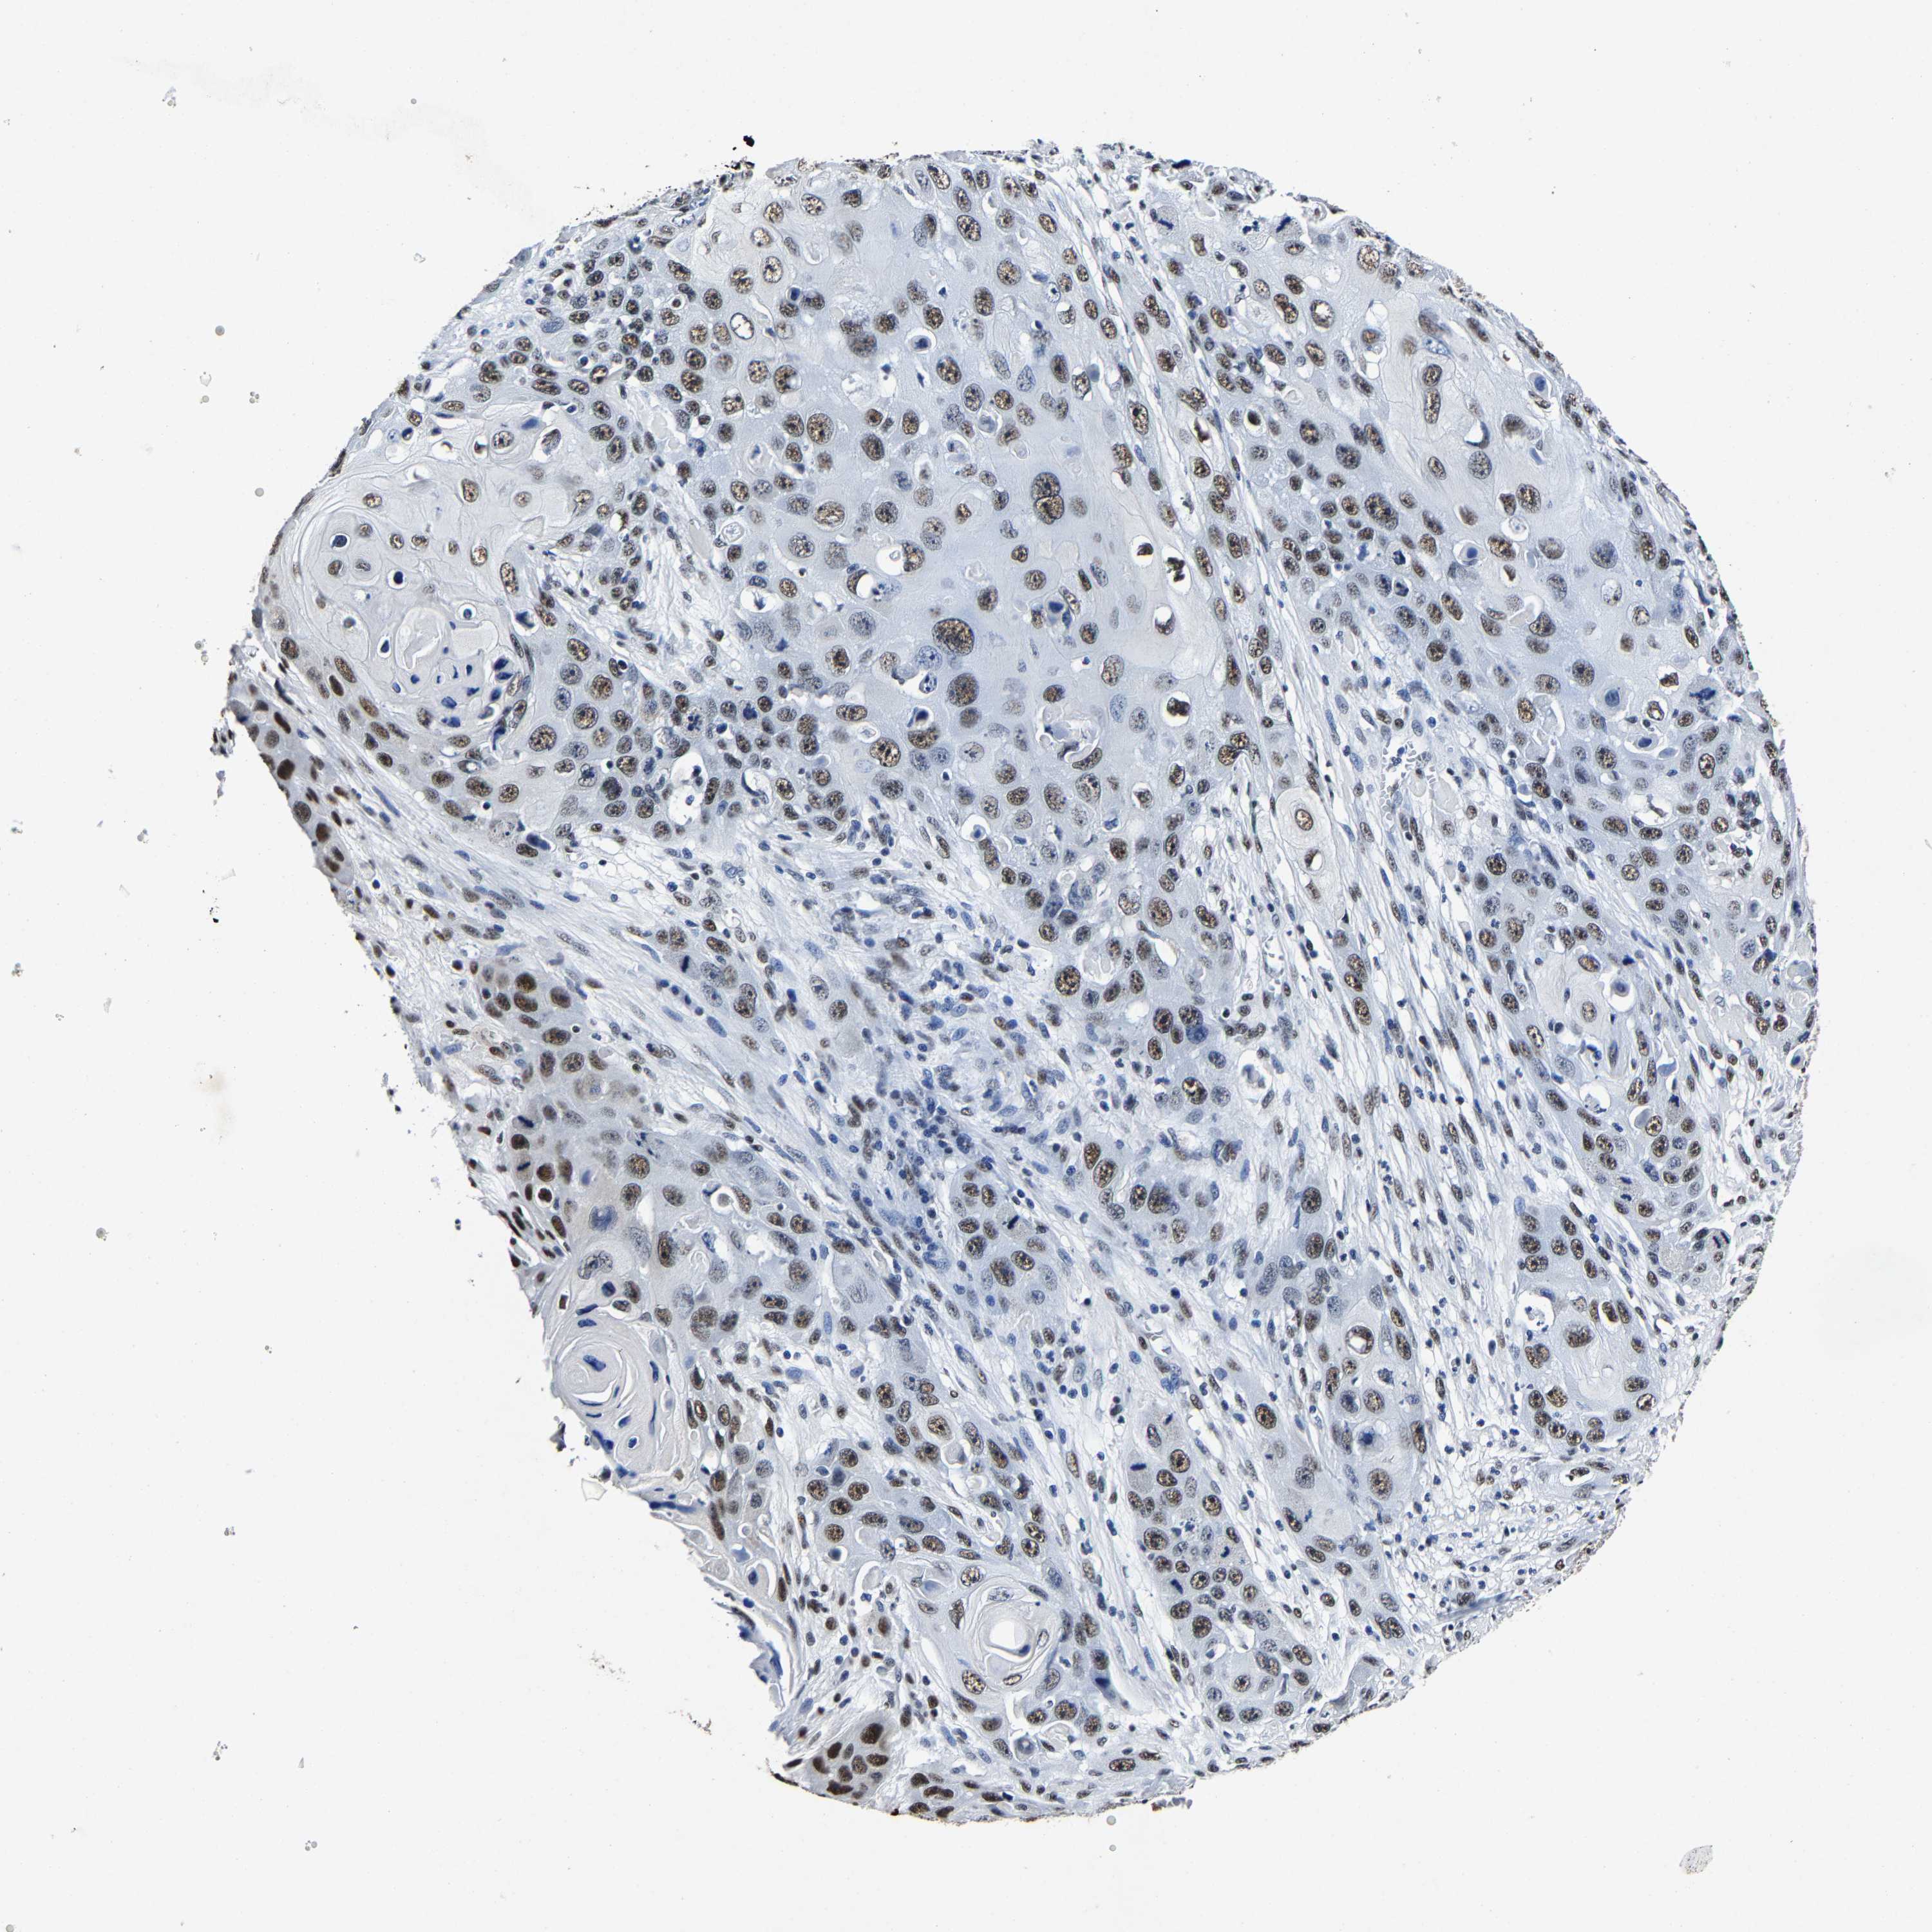

SKIN CANCER - Protein expressioni

A mouse-over function shows sample information and annotation data. Click on an image to view it in a full screen mode. Samples can be filtered based on level of antibody staining by selecting one or several of the following categories: high, medium, low and not detected. The assay and annotation is described here.

Antibody stainingi

Antibody staining in the annotated cell types in the current human tissue is reported as not detected, low, medium, or high, based on conventional immunohistochemistry profiling in selected tissues. This score is based on the combination of the staining intensity and fraction of stained cells.

Each image is clickable and will lead to virtual microscopy that enables deeper exploration of all samples and also displays staining intensity scores, fraction scores and subcellular localization as well as patient and tissue information for each sample.

Antibody HPA020448

Staining

High

Intensity

Strong

Quantity

>75%

Location

Nuclear

Squamous cell carcinoma, NOS

Squamous cell carcinoma, metastatic, NOS